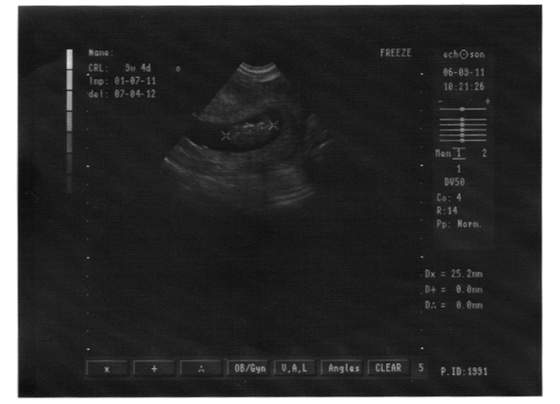

bejbik.jpg

dzisiejsza fotka naszego malucha :) niestety nie wiem dokładnie co oznaczają te wszystkie skróty,ale wychodzi na to że to 9tydz 4dzień i że ma 25,2mm. Ma wszystko na swoim miejscu ;) niestety na usg widać właściwie tylko plecki ;)